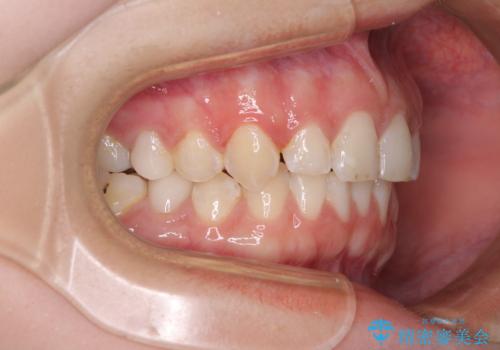

- 前歯の歯列不正を気にして来院された患者様です。

インビザラインでの矯正治療を希望されていましたが、奥歯の咬み合わせがインビザライン単独では改善困難と判断されたので、補助装置を併用することとしました。

まずは裏側の装置やワイヤー矯正を用いて歯列幅の狭い上顎を側方に拡大しつつ全体を後方に移動させ、その後インビザラインにて歯列を整えることとしました。